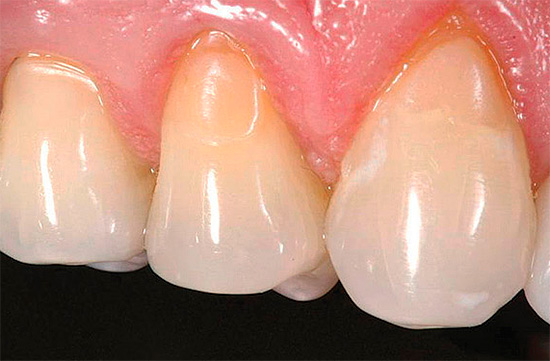

Abaixo estão algumas fotos com exemplos de cárie cervical:

Muitas pessoas começam a levar a cárie cervical a sério e as razões que a causam somente quando o problema é claramente evidente no reflexo no espelho e causa inconvenientes estéticos naturais. A zona de sorriso para pessoas que precisam de comunicação para implementar determinadas tarefas é de particular valor. E como a cárie cervical geralmente é localizada precisamente nos dentes da frente, há uma necessidade urgente de devolver o componente estético.

A foto abaixo mostra um exemplo típico de cárie cervical nos dentes da frente: